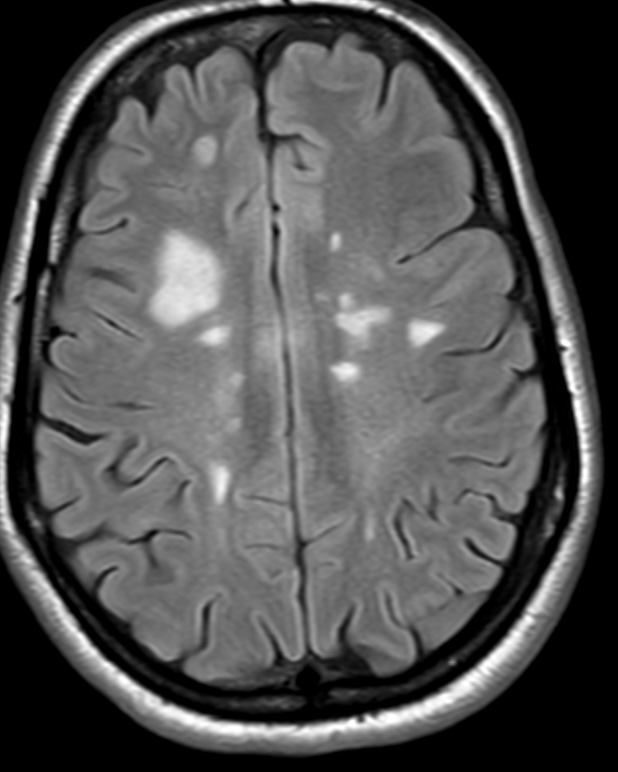

معايير ماكدونالد هي مجموعة من الإرشادات التي تتضمن التقييمات السريرية والمخبرية، بالإضافة إلى بيانات التصوير بالرنين المغناطيسي (MRI)، لتحديد تشخيص مرض التصلب العصبي المتعدد.

الانتشار في الفضاء

الانتشار في الفضاء يعني أن الضرر العصبي يحدث في أجزاء متعددة من الجهاز العصبي المركزي. على وجه التحديد، تحدد معايير 2017 الانتشار في الفضاء على أنه آفات مرضية في منطقتين على الأقل من أربع مناطق في الجهاز العصبي. تشمل هذه المناطق ثلاث مناطق من الدماغ (محيط…

وبالمثل، فإن الانتشار في الوقت المناسب يعني أن الضرر العصبي يحدث في أكثر من نقطة زمنية واحدة. ويمكن إثبات ذلك إما من خلال تفاقم المرض الثاني، أو ظهور آفات جديدة في فحوصات التصوير بالرنين المغناطيسي، أو من خلال أدلة واضحة على تلف الدماغ الذي حدث في أوقات…